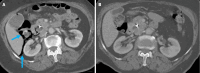

Endoscopic retrograde cholangiopancreatography (ERCP) is a cornerstone procedure for the diagnosis and management of pancreatic and hepatobiliary diseases. Although its diagnostic role has been increasingly supplanted by noninvasive imaging modalities such as magnetic resonance imaging (MRI) and magnetic resonance cholangiopancreatography, the therapeutic applications of ERCP have continued to expand. ERCP is widely used and has a generally favorable safety profile. However, it is important to recognize expected post-procedural imaging findings and serious complications that can arise. The increasing complexity of therapeutic interventions and the growing volume of procedures have led to a higher incidence of complications that often present with overlapping clinical and laboratory features, underscoring the critical role of imaging in differential diagnosis. This review focused on the typical normal ERCP findings and the imaging characteristics of common complications, including pancreatitis, bleeding, ERCP-related infections, perforations, and stent-related complications. Computed tomography (CT) is particularly valuable in timely recognition, management, and surgical decision-making for these complications. Furthermore, MRI offers a radiation-free alternative for managing complications in selected patients. Therefore, radiological modalities, particularly CT and MRI, are critical tools for the rapid diagnosis, management, and surgical decision-making processes for post-ERCP complications.